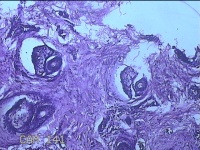

性别

男

年龄

23岁

临床诊断

右耳部肿物

一般病史

右耳前无痛性肿物20余年。

标本名称

大体所见

灰白暗红色肿物0.7x1.5x0.2cm一个,表面糜烂。